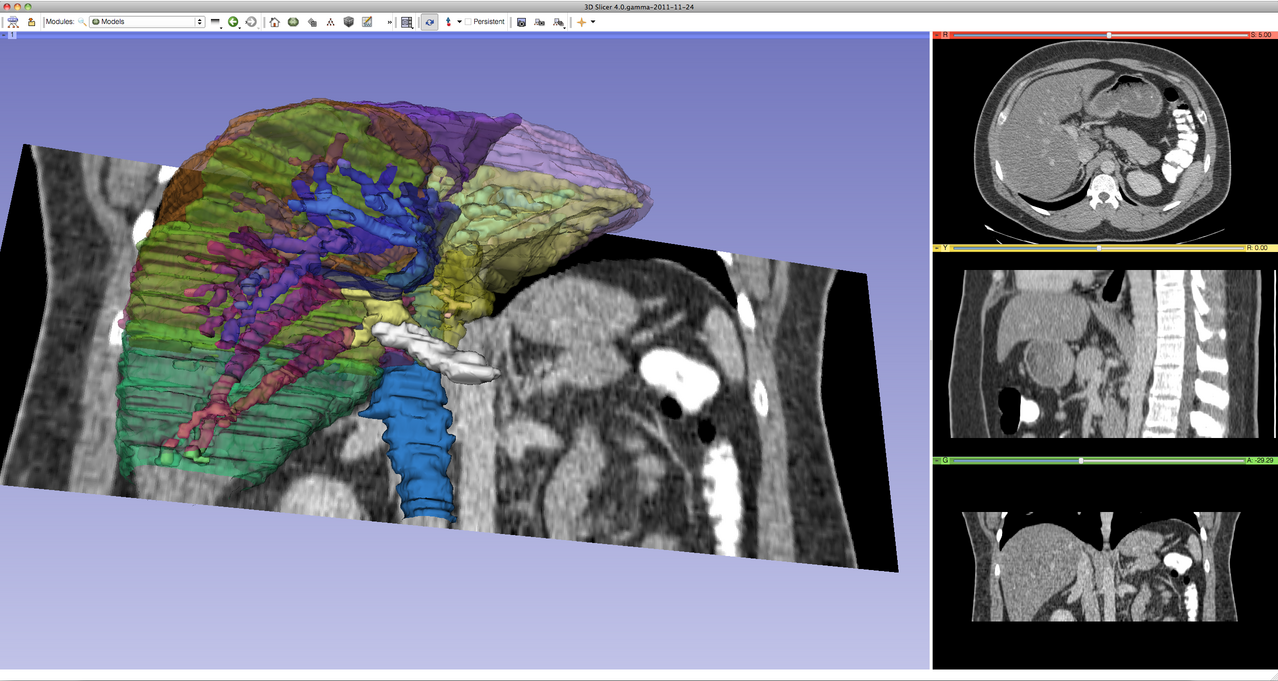

Introduction to the advanced 3D visualization capabilities of 3D Slicer.

Shows how to use the Segment Editor module for segmenting heart ventricles, atria, and great vessels from cardiac CT volumes.

Provides step-by-step description of useful segmentation techniques. Segmentation tutorials for common tasks, such as skin surface extraction, craniotomy (splitting segments), sorta segmentation, cerebral vessel segmentation by subtraction, segmentation on arbitrarily oriented slices, skull stripping.